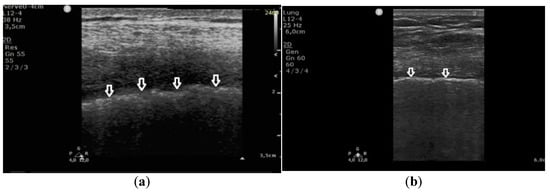

In patients with pulmonary fibrosis, in all 381 points evaluating the pleural line, the following abnormalities were detected: coexisting irregularity and fragmentation of the pleural line in 68% (259 localizations) and blurred pleural line in 22% (84) of all evaluated points; the apparent thickening of the pleural line (>2 mm) was detected in only one (0.26%) area. Irregular and/or fragmented pleural line was present in 97% (230 out of 236) of the patients in the group in which B-lines converted into Z-lines (when the frequency was changed from 2 MHz to 6 MHz) (Figure 3).

These findings indicate that an irregular and fragmented pleural line is a feature that differentiates pulmonary fibrosis from cardiogenic pulmonary edema. Detection of this feature in a single evaluated point allows for diagnosis of pulmonary fibrosis with a specificity of 99%, a sensitivity of 68%, PPV 99%, NPV 68%, LR(+) 60, and LR(−) 0.32, at AUC = 0.836 and p = 0.0002.

Figure 3. Linear transducer used for the evaluation of pleural line abnormalities: (a) irregular, blurred pleural line (white arrows), coarse in appearance, in pulmonary fibrosis; (b) regular pleural line, with preserved echogenicity (white arrows), in pulmonary edema.